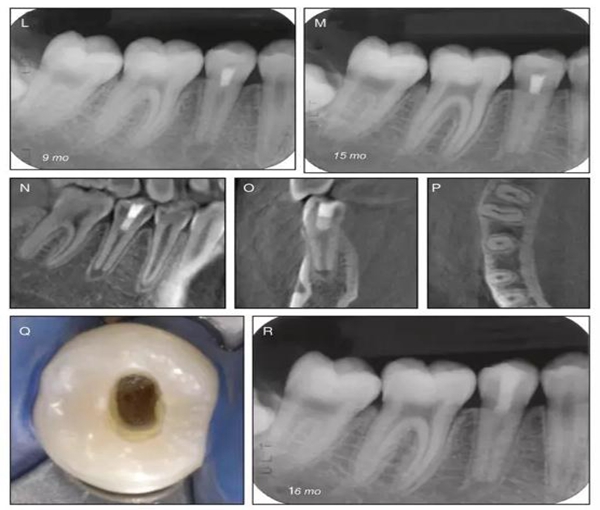

原則上年輕恒牙的牙髓治療應盡可能以保存活髓的方式以便不影響牙根繼續(xù)發(fā)育。本文3個病例均描述了根尖尚未發(fā)育完成的下頜前磨牙被確診為牙髓壞死伴有大面積根尖病損,治療過程中在根管內(nèi)發(fā)現(xiàn)了部分活髓,而采用活髓切斷后都取得了很好的療效。